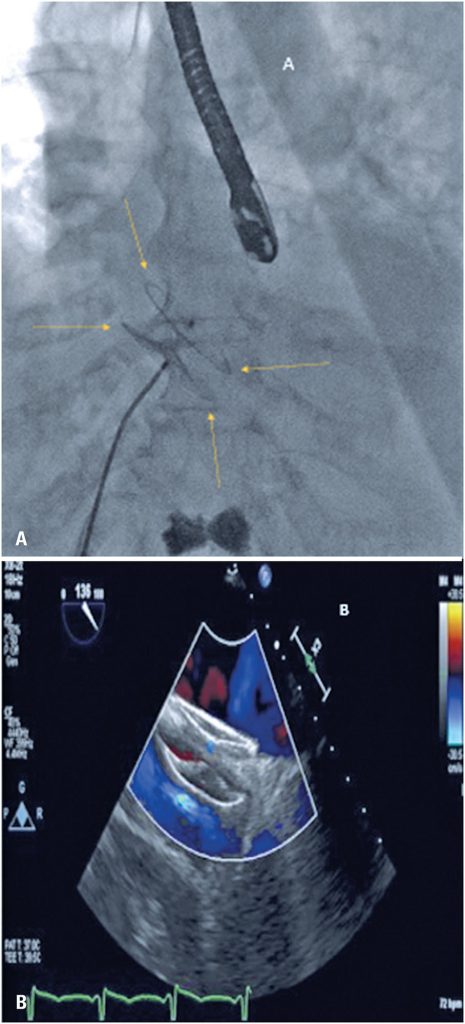

Platypnea-orthodeoxia syndrome: echocardiography-guided percutaneous treatment

Platypnea-orthodeoxia syndrome, first described in 1949, is a rare clinical condition characterized by positional dyspnea and oxygen desaturation in the upright position that improves when lying down. Herein, we report the case of an 86-year-old patient who experienced episodes of dyspnea on assuming an upright position, which limited her daily activities. The patient’s oxygen saturation was 82% in the standing position and 91% in the supine position. During diagnostic investigation, a patent foramen ovale was identified using transesophageal echocardiography. The patient underwent percutaneous patent foramen ovale closure with an Amplatzer device, which resulted in significant improvement in her symptoms and oxygen saturation. Diagnosis of this condition requires a high index of clinical suspicion and is confirmed when the syndrome’s signs and symptoms correlate with the presence of a right-to-left interatrial shunt. It is predominantly diagnosed using echocardiography with agitated saline injection.